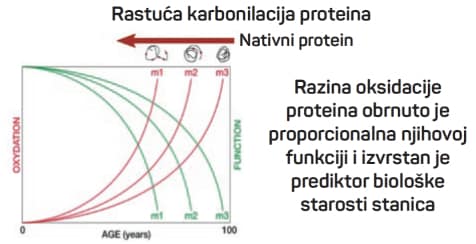

Oksidacija proteina jedan je od najboljih markera starenja i upalnih procesa. Metalni nanoklasteri: Novi detektori karbonilacije proteina 2D-oxyDIGE gel proteina ljudske plazme.

Karbonilacija proteina može se detektirati i mjeriti pomoću 2D-oxyDIGE metode koja koristi specifičnu fluorescentnu probu vezanu na hidrazid koji reagira s karbonilnom skupinom.

Kao model koristi se protein SOD1 koji je vezan uz pojavu teške neurodegenerativne bolesti amiotrofične lateralne skleroze (ALS). Odabrani su mutanti SOD1 za koje se pretpostavlja da će imati veću osjetljivost na karbonilaciju i stvaranje agregata.

Kako bi se poboljšala specifičnost i osjetljivost tehnike, razvijaju se nanoklasteri koji zamjenjuju te ci-hidrazidne boje.